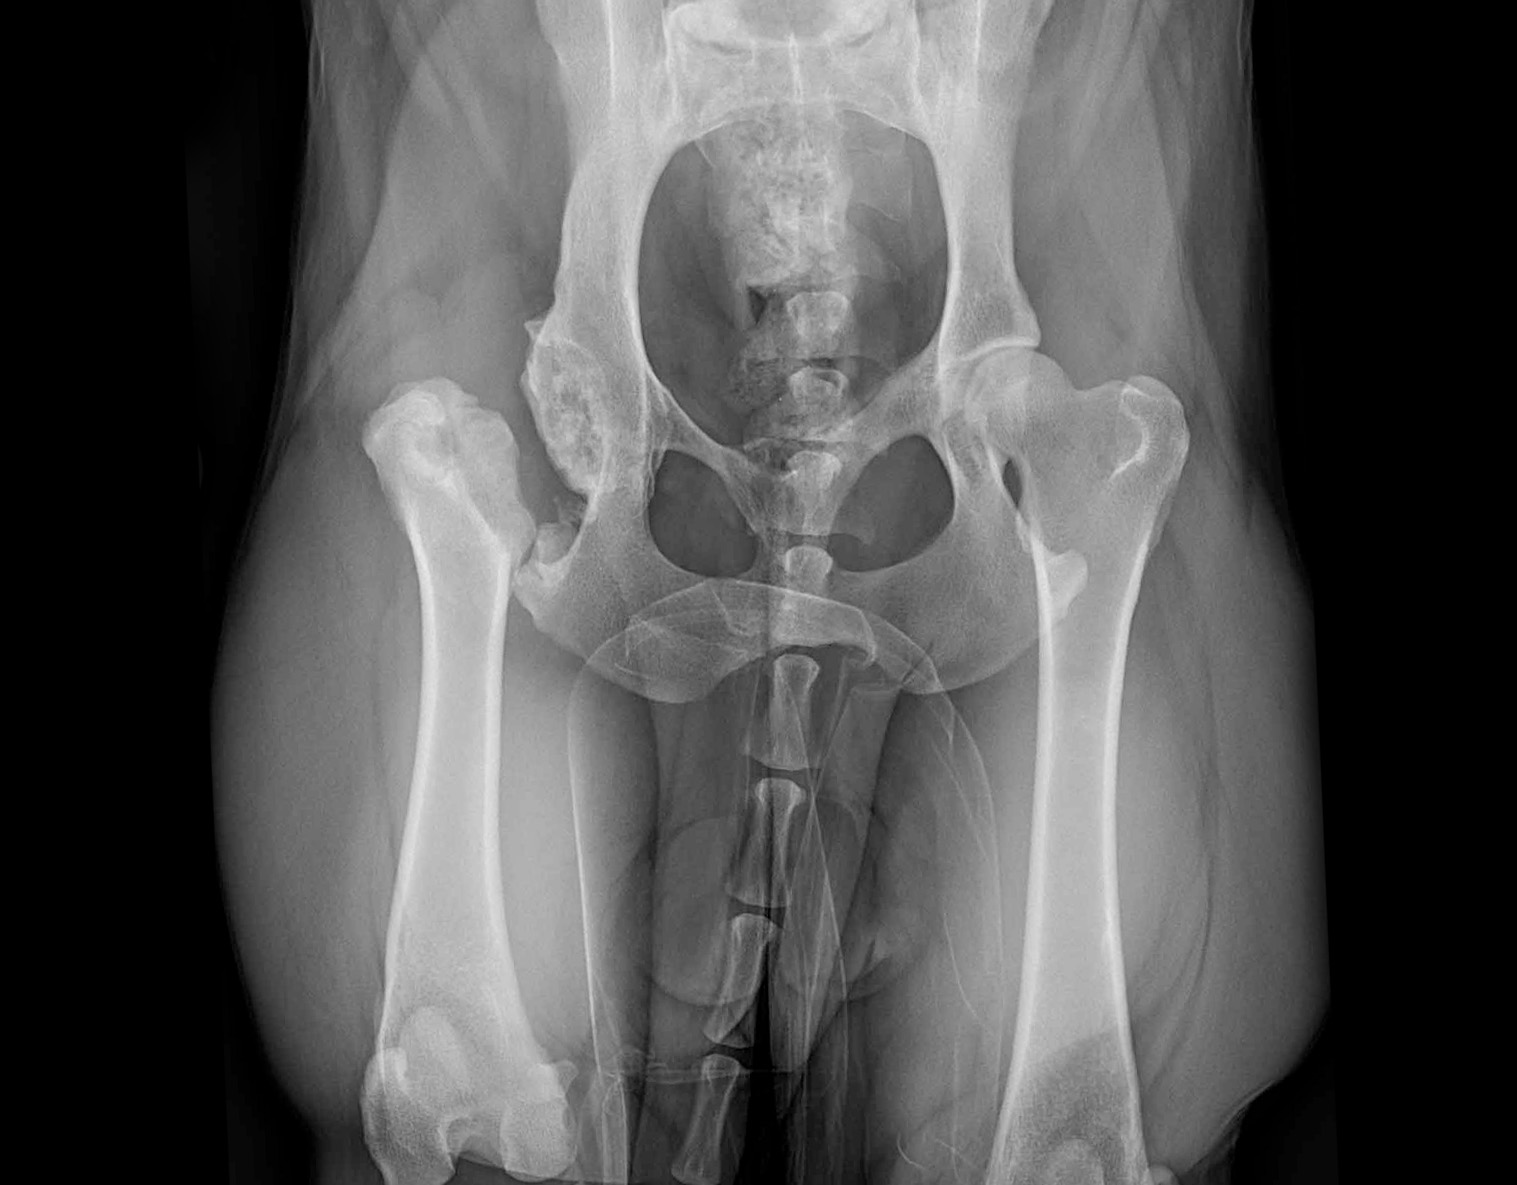

“Bailey was rescued when she was approximately 2 years old. Her owner noticed hind-limb lameness and had her evaluated. X-rays revealed a fractured hip at which time a Femoral Head Ostectomy (FHO) was performed. Bailey healed well and lead an active lifestyle for 4 years before pain returned. She was then referred to Dr. Dyce who confirmed she was a good candidate for Total Hip Replacement. The surgery was successful and now, at 4 years post-op and 10 years of age, Bailey acts like a young pup! She goes on 12 mile runs with no apparent pain or issues, plays fetch with reckless abandon, leaps, and jumps.”